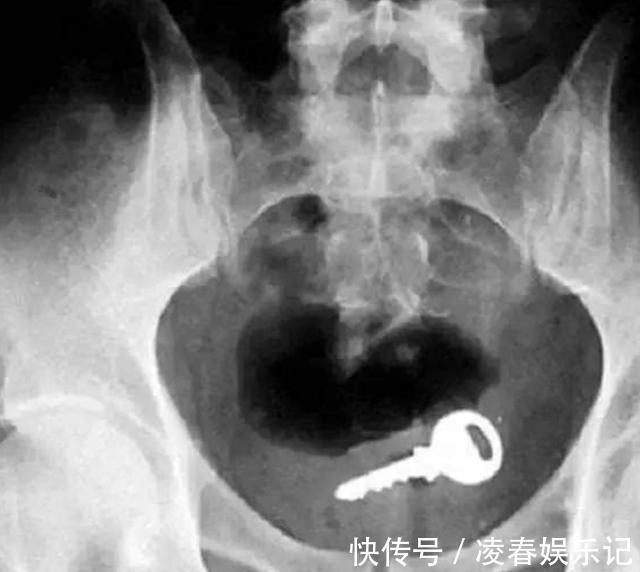

过了一段时间孩子突然生病发烧,一家人担心不已,赶紧把孩子带去医院。经过专业仪器的检查,医生怒斥一家人的无知,让他们赶紧把孩子手上的手镯摘掉。孩子因为这个手镯已经出现了重金属中毒的现象。

如果是纯银的手镯并没有关系,可这个手镯是祖上传下来的,由于制作工艺并不精良,因此里面掺了一些其他金属的杂质。孩子没事的时候就喜欢舔这个手镯玩,导致手镯变得越来越亮,孩子的身体也变得越来越差。父母要学会如何保护孩子的安全⒈清扫家中的危险物品如果家中来了一个可爱的小生命,父母一定要对家中的布局进行一次大扫除,避免一些危险的尖锐物品会伤到孩子的身体。同时也要把一些电池纽扣之类的东西放到比较高的地方,不要让孩子轻易碰到。因为小孩子根本就不知道这些东西的危险性,很容易吞到肚子里。